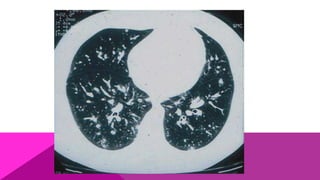

MODERADA

La sintomatología aumenta, simulando una

neumonía atípica; el cuadro respiratorio es más

evidente, con presencia de tos, estertores y

discreta disnea; el ataque al estado general viene

acompañado por fiebre moderada y constante,

cefalea, dolores musculares y óseos. A los rayos X

se observa aumento de volumen de los ganglios

hiliares.

GRAVE

Es bastante parecida a los casos de tuberculosis;

se presenta como un cuadro muy agudo,

caracterizado por abundante tos con expectoración

mucoide, hemoptisis, marcada disnea; estertores

crepitantes o subcrepitantes, sibilancias y ataque

al estado general, caracterizado por astenia,

cefalea intensa, fiebre aguda y diaforesis; algunos

casos pueden presentar diarrea, que junto con la

alta temperatura se confunde fácilmente con fiebre

tifoidea.

MODERADA La sintomatología aumenta,simulando una neumonía atípica; el cuadro respiratorio es más evidente, con presencia de tos, estertores y discreta disnea; el ataque al estado general viene acompañado por fiebre moderada y constante, cefalea, dolores musculares y óseos. A los rayos X se observa aumento de volumen de los ganglios hiliares.

GRAVE Es bastante parecidaa los casos de tuberculosis; se presenta como un cuadro muy agudo, caracterizado por abundante tos con expectoración mucoide, hemoptisis, marcada disnea; estertores crepitantes o subcrepitantes, sibilancias y ataque al estado general, caracterizado por astenia, cefalea intensa, fiebre aguda y diaforesis; algunos casos pueden presentar diarrea, que junto con la alta temperatura se confunde fácilmente con fiebre tifoidea.